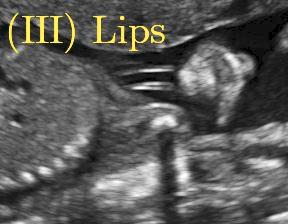

Fig. 6 compares the shadow confidence maps of the state-of-the-art methods and the proposed methods. RW and have the same parameters as used for Table I. The shadow confidence maps of the baseline, the proposed method and the proposedAG method are generated directly from input shadow images by confidence estimation networks. Overall, the proposed method and the proposedAG method achieve more visually reasonable shadow confidence estimation than the baseline and the state-of-the-art on different anatomical structures shown in Fig. 6. The proposed method and the proposedAG method are able to highlight multiple shadow regions while the RW algorithm shows limitations for most cases, especially for disjoint shadow regions.

Row I in Fig. 6 shows a fetal brain image from . The confidence estimation of shadow regions from the baseline, the proposed method and the proposedAG method are similarly accurate since we use fetal brain images to train the confidence estimation networks in these three methods. These outperform [16] and [22]. Rows (II-IV) in Fig. 6 show shadow confidence maps of non-brain anatomy from , including lips, abdominal and cardiac. The baseline failed on unseen data during inference. However, the proposed methods are able to generate accurate shadow confidence maps because of the generalized shadow features obtained by the shadow-seg module. Furthermore, the “Lips” example shows that our method is capable of detecting weaker shadow regions that have not been annotated in manual segmentation. This indicates that the confidence estimation network has learned general properties of shadow regions.